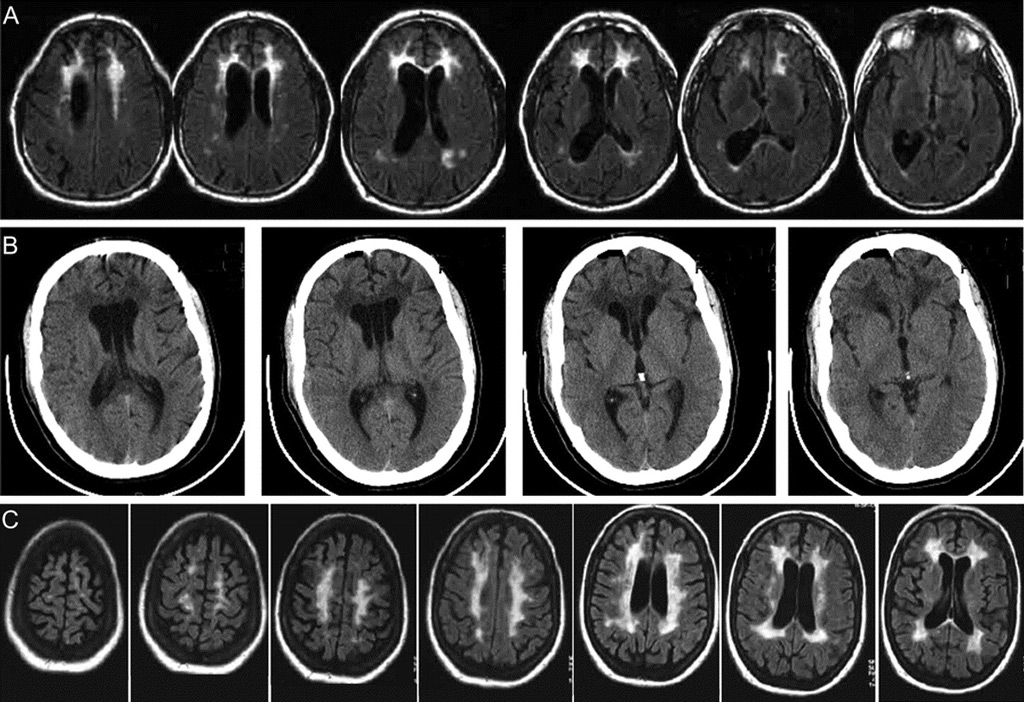

Врачи отмечают, что глиоз головного мозга представляет собой реакцию на повреждение нервной ткани, что может быть вызвано различными факторами, такими как травмы, инсульты, инфекции или хронические заболевания. Признаки глиоза могут варьироваться в зависимости от локализации и степени поражения, включая головные боли, нарушения памяти, изменения в поведении и моторные расстройства. Для диагностики заболевания используются методы нейровизуализации, такие как МРТ, которые позволяют выявить участки глиоза. Лечение, как правило, направлено на устранение первопричины и может включать медикаментозную терапию, реабилитацию и в некоторых случаях хирургическое вмешательство. Врачи подчеркивают важность ранней диагностики и комплексного подхода к лечению для улучшения качества жизни пациентов.

Глиоз головного мозга — это процесс замещения нейронов глиальными клетками, который может возникать по различным причинам, включая травмы, инсульты и воспалительные заболевания. Люди, столкнувшиеся с этой проблемой, часто отмечают разнообразные симптомы, такие как головные боли, нарушения памяти и координации. Диагностика глиоза обычно включает МРТ, которое позволяет визуализировать изменения в мозговой ткани. Лечение зависит от причины и степени глиоза: в некоторых случаях достаточно наблюдения, в других — требуется медикаментозная терапия или даже хирургическое вмешательство. Важно помнить, что ранняя диагностика и адекватное лечение могут значительно улучшить качество жизни пациентов.

Перед началом лечения глиоза важно провести тщательное обследование пациента, особенно головного мозга. Для этого применяются современные диагностические методы, такие как МРТ, КТ и ангиография. Наиболее предпочтительным вариантом является магнитно-резонансная томография, так как она предоставляет полную информацию о количестве очагов глиоза, их размерах, расположении, степени поражения и состоянии соседних структур без необходимости в дополнительных исследованиях.

Глиозные очаги. Причины: перенесённые инсульты (микро- или крупные), травмы, воспаления, нейроинфекции, токсические влияния (алкоголь, наркотики), рассеянный склероз и другие. МРТ-характеристика: на T2-взвешенных (и FLAIR) изображениях глиоз проявляется как гиперинтенсивные (более «светлые») зоны.

Глиоз можно определить с помощью нейровизуализационных методов, таких как магнитно-резонансная томография (МРТ) или компьютерная томография (КТ), которые позволяют выявить изменения в мозговой ткани, характерные для этого состояния. Также важны клинические данные, включая симптомы и историю болезни пациента, а в некоторых случаях может потребоваться биопсия для подтверждения диагноза.